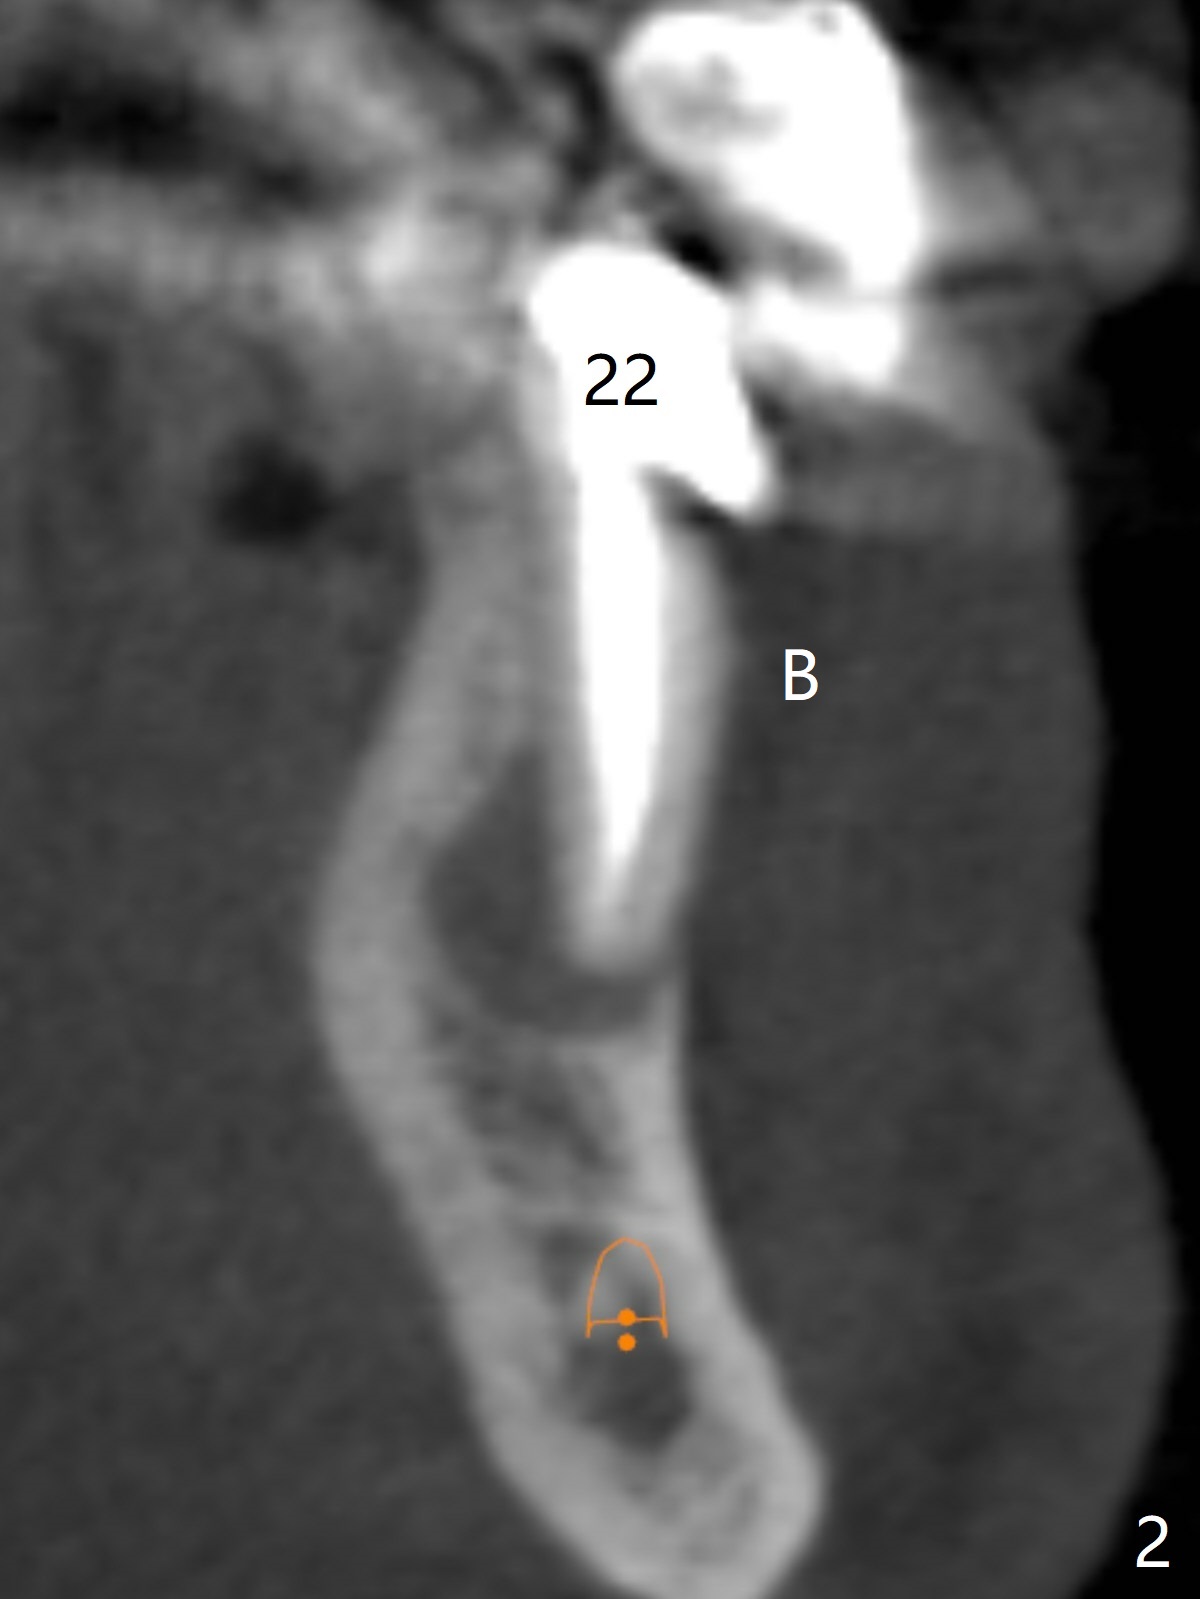

A 61-year-old man has poor dentition (#7 10), requesting extraction of the tooth #22 with root split (Fig.1 *). CT taken 1.5 years earlier (before crown fracture) shows missing buccal plate (Fig.2 B). After extraction, a smallest, longest 2-piece implant (3.8x18 mm) will be chosen to gain ~ 3 mm apical native bone for primary stability; to obtain a 2 mm buccal gap (Fig.3 red line), the implant will be placed as lingual as possible. To achieve the buccal gap, the buccal portion of the lingual plate (Fig.3 L) will be removed (Fig.4 black area) using Lindamann bur. For restoration, a 15 or 25 degree angled abutment may be used (Fig.3,4). If the root is stable, socket shield will be performed.